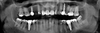

L'implantologie dentaire est la solution la plus fiable et durable pour remplacer une ou plusieurs dents manquantes.

Un implant dentaire est une racine artificielle, généralement en titane, insérée dans l'os de la mâchoire pour remplacer une dent manquante. Il sert de support stable et durable à une prothèse dentaire (couronne, bridge ou dent fixe), offrant ainsi une solution esthétique et fonctionnelle.